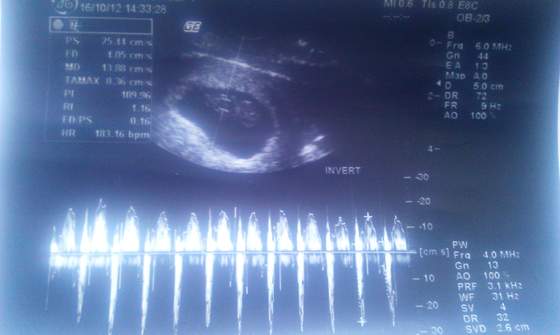

Ból powoli zaczął się zmniejszać, na 15 wczoraj pojechałam do gin, okazało się że z maluchem wszystko w porzadku, ale odetchnęłam, bardzo się bałam!

nawet rączką nam pomachał!

8t4d.jpg8t4d_16102012.jpg8t4d_16102012a.jpg